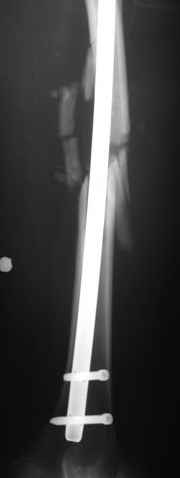

Единственно что наблюдал - замедленная консолидация, судя по серийным Рг граммам. В приведенном случае прии вялом мозолееобразовании сделал ошибку, решившись динамизировать гвоздь - перелом сросся со значительным укорочением бедра - повторная хирургия по удлинению бедра и проксимальным запиранием, больной мобилизован и вполне доволен(кстати заметить больной с ВИЧ инфекцией - изначально скомпрометированный иммунитет и несмотря на это, всё прошло без костной и мягкотканной инфекции.

Думаю, что новая технология штифитования, сокращение времени с момента травмы до стабилизации перелома, современная антибактериальная терапия должны менять и подход к лечению огнестрельных повреждений, спасибо Джолдасу - представил свой случай на форуме когда то штифтования перлома бедра при огнестреле.